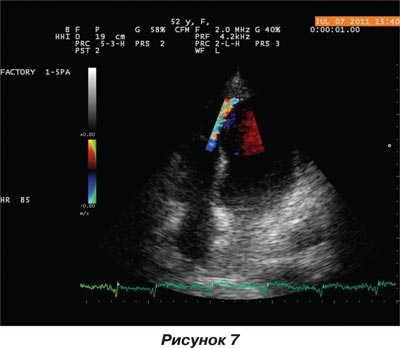

Оперативное вмешательство по устранению дефекта межжелудочковой перегородки проведено успешно. Больная в удовлетворительном состоянии переведена в ННЦ «Институт кардиологии им. Н.Д. Стражеско» в отделение инфаркта миокарда и восстановительного лечения. При проведеннии эхокардиографического исследования выявлено закрытие места разрыва межжелудочковой перегородки тканью обтуратора, кровоток между левым и правым желудочками сердца минимальный (рис. 6, 7).